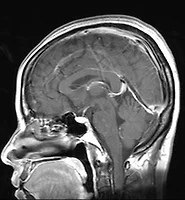

뇌혈관질환이란 우리의 뇌에 혈액을 공급하고 있는 혈관이 막히거나 터짐으로써 그 부분의 뇌가 손상되어 나타나는 신경학적 증상을 말한다.

뇌혈관질환은 "뇌혈관의 이상에 의해 갑자기 발생한 뇌기능장애를 일으켜 쓰러지는 병”으로서 발증 형태에 따라 두개(頭蓋)내의 혈관일부가 파손되어 출혈하는 출혈성(出血性, hemorrhagic)과 혈관속의 혈액흐름이 나빠지거나 막히기도 하는 허혈성(虛血性, ischemic) 뇌혈관질환으로 구별된다.

뇌혈관이 터져서 생기는 두개강내 출혈 (intracranial hemorrhage)을 동반하는 출혈성 뇌질환 (hemorrhagic cerebrovascular disease)은 주로 고혈압과 뇌혈관괴사에 의해 발생하며, 출혈이 고인 부위에 따라 뇌안으로 피가 터져 번지는 뇌실질내출혈과 뇌 밖의 지주막하강(蜘蛛膜下腔)으로 터지는 지주막하 출혈로 나뉘어 지며, 그 원인에 따라 고혈압성(高血壓性), 뇌동맥류(腦動脈瘤), 뇌동정맥 기형(腦動靜脈 畸形)등으로 구분하기도 한다.

뇌혈관이 막혀서 허혈성 병소 (ischemic lesion)를 일으키는 폐쇄성 뇌혈관질환 (occlusive cerebrovascular disease)은 발생기전에 따라 뇌색전(惱塞栓), 뇌혈전(惱血栓), 뇌혈색전(惱血塞栓)등으로 구분하기도 하며, 증상의 양상에 따라 일과성 허혈, 가역성 허혈성 신경학적 결손, 진행성 뇌허혈증, 고정성 뇌졸중으로 구분된다.

(다) 뇌경색

혈전이나 색전에 의하여 뇌혈관이 막히는 것을 말하며, 뇌혈관이 부분적으로 또는 완전히 막힘으로서 정상적인 혈액순환이 이루어지지 않음으로서 뇌에 산소와 영양공급이 이루어지지 않아 발병 부위의 뇌조직이 괴사되어 기능이 저하되거나 소실된다.

주원인은 동맥경화이며 그 외 원인으로 심장질환, 혈액질환, 혈관질환, 저산소증 등이 있음.